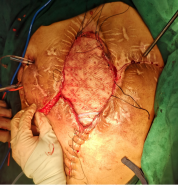

经过了充分的术前评估和讨论后于2018年8月21日进行确定性手术治疗,手术过程是惊心动魄的一天,手术难度非常大,包括复杂肠粘连松解、多发肠瘘切除、消化道重建与腹壁重建,手术历时10个小时。手术的难点是十二指肠瘘和腹壁缺损的处理。因为十二指肠瘘口范围较大,而且是炎性瘢痕组织,不能单纯缝合,十二指肠切除极有可能造成危及病人生命的大出血,因此李元新主任游离了一部分小肠与十二指肠瘘口吻合,并预想到术后会发生吻合口瘘,因此在吻合口周围放置好引流管,术后虽然确实发生了十二指肠瘘,但经过保守治疗最终用生物蛋白胶进行封堵成功。

另一手术难点是腹壁重建,因为本病人经历多次手术,两侧腹壁及胸壁瘢痕组织严重,加之多次放置多跟引流管,导致腹壁两侧无法游离及转移皮瓣,导致皮肤无法关闭,李元新主任手术团队再次应用大网膜替代皮肤组织的策略成功关闭患者腹腔,避免了诸多相关并发症的再次发生。